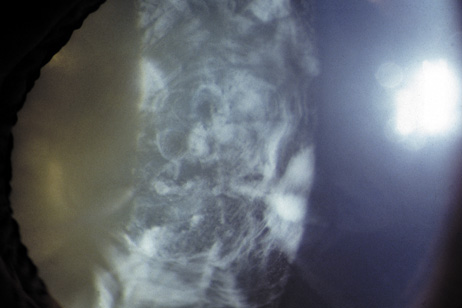

The dense bilateral lens opacities may present as a biconvex-shaped cataract or as posterior, polar, nuclear, or total cataract. The discoid lens shape may result from loss of lens material due to a posterior lens capsule defect4 or defective lens fiber formation and subsequent degeneration.5 The cataracts are present at birth, and glaucoma may be present congenitally or develop within the first 3 years of life. Other ocular findings may include corneal opacity, mitotic pupil, enophthalmos, and hypotonia.6 The cognitive impairment presents with a discrete behavioral phenotype that includes temper tantrums, irritability, complex repetitive behaviors, and unusual mannerisms. Severe renal Fanconi's syndrome may lead to progressive renal impairment. Most boys will develop a distinctive facies and habitus, and attain a height of less than 5 feet because of developmental retardation. Female carriers manifest characteristic but usually asymptomatic lenticular opacities that will correctly identify carrier status with 100% sensitivity in postpubertal females. These opacities are typically small, irregularly shaped, off-white or gray in color, nonrefractile in appearance, and distributed around the lens equator, more anteriorly than posteriorly (Figs. 1 and 2). Most importantly, and distinctively, these opacities are clustered in radial bands or wedges in the peripheral cortex of the lens and are visible by retroillumination. Typically, the opacities are moderately dense for one or two clock-hours, are then less numerous or even absent for another clock-hour or two, and so on. These opacities must be differentiated from the polychromatic, iridescent “crystals” found in Steinert's myotonic dystrophy (DM), gray-white random opacities in carriers of X-linked adrenoleukodystrophy, sutural opacities in Nance-Horan's (NH) syndrome, snowflake granules beneath the anterior and posterior capsule in diabetes mellitus, highly uniform white dots of hypoparathyroidism, and equatorial opacities in cataracta coronaria or ceruleana. Some females also manifest a dense white, central, posterior cortical cataract in the precapsular area. Although the posterior central cataract is apparently congenital, the equatorial and anterior cortical punctate opacities are uncommon in prepubertal female Lowe's syndrome carriers.7 Carrier status may also be confirmed by DNA diagnosis.

Fig. 1. OCRL. Female carrier with typical small, irregularly shaped, off-white or gray, nonrefractile opacities in the anterior lens cortex, slit-lamp view. (Courtesy of Dr. R.A. Lewis, Baylor College, Houston, Texas.)